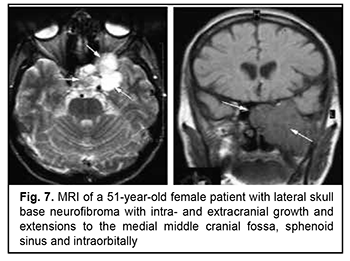

Craniofacial meningioma usually develops due to incompletely removed olfactory fossa meningioma, sphenoid wing meningioma or middle cranial fossa meningioma. A meningioma in any of the above locations, if incompletely removed (particularly, incompletely removed skull base infiltration) may become the origin of the subsequent growth on the inner and outer skull surfaces. We noted intra- and extra-cranial growth of primary meningioma at the ethmoid labyrinth, medial middle cranial fossa and medial posterior cranial fossa. Fig. 6 exemplifies the further spread of the sphenoid wing meningioma to the middle cranial fossa floor, cavernous and sphenoid sinuses, orbit, infratemporal and pterygopalatine fossae, and nasal cavity after incomplete tumor removal. It is noteworthy that, within the field of ophthalmic oncology, sphenoid wing meningiomas constitute a major portion of the large tumors of the anterior skull base and orbit. The tumor extends intracranially and extracranially from the pterygopalatine fossa, leading to destruction of the floor of the medial middle cranial fossa and the involvement of the cavernous sinus (Figs. 7, 8).